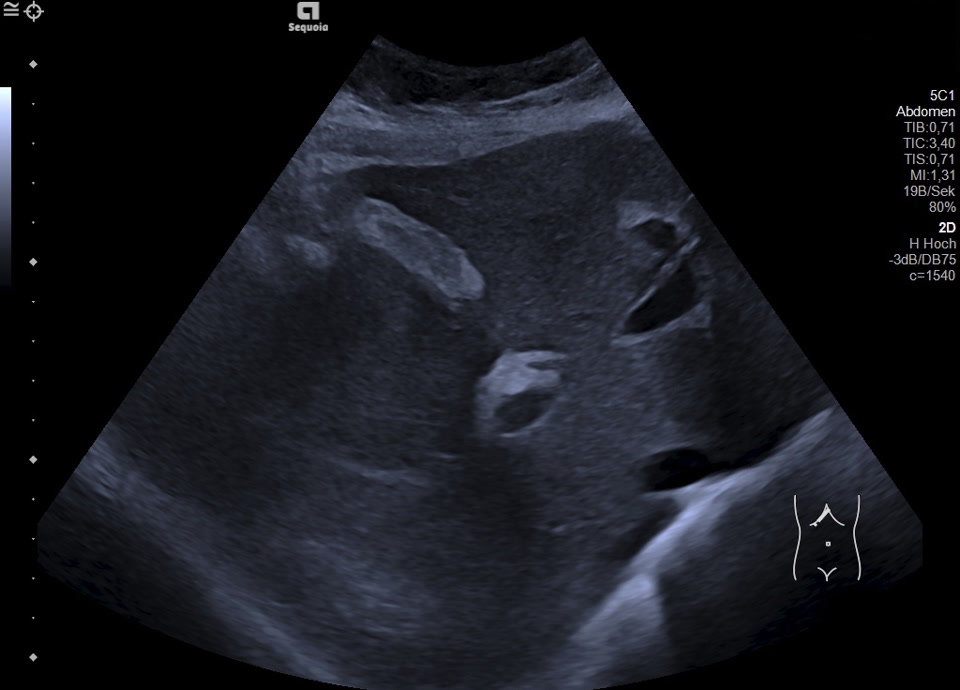

Normal Gallbladder

• Gallbladder in longitudinal view